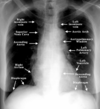

This is a normal ______ X-ray view (woman patient) of the chest.

PA

In PA and lateral chest X-rays, the heart shows up very well because the ________ isn’t so bright that it obscures the heart.

vertebral column

NORMAL PA/LATERAL CXR

A satisfactory CXR includes all _____ribs, the diaphragm, both clavicles.

NORMAL PA/LATERAL CXR

The ____ should be of optimal penetration.

The ___ follows the periphery of the film first, observing soft tissues and rib contours one by one, then the diaphragm.

Next, the ____ of the mediastinum.

Lastly, the ___ ___.

film, eye, contours, lung fields